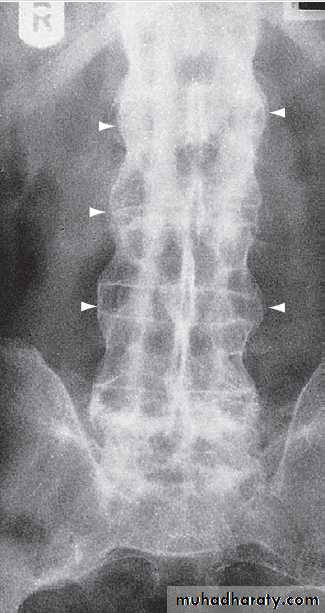

Plain radiographyShow changes of many bone and joint diseases . Radiographs are of diagnostic value in osteoarthritis

(OA), where they demonstrate joint space narrowing

that tends to be focal rather than widespread, as in

inflammatory arthritis. Other features of OA detected on

X-ray include osteophytes, subchondral sclerosis, bone

cysts and calcified loose bodies within the synovium . Radiographs may show erosions and sclerosis of the sacroiliac joints and syndesmophytes in the spine in seronegative spondyloarthritis. In peripheral joints, so-called proliferative erosions, associated with new bone formation and a periosteal reaction, may be observed.